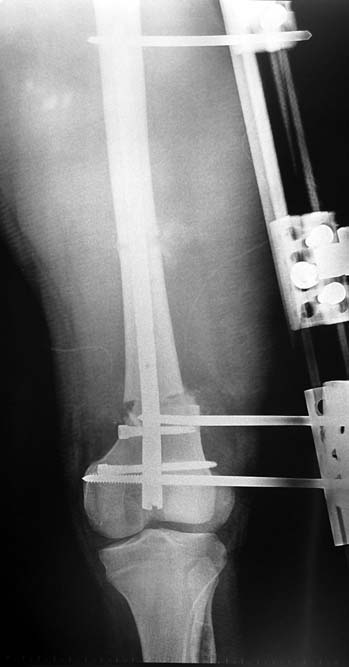

3. POSTTRAUMATIC LOWER LIMB SHORTNESS (MALUNION)

This type of shortness occurs after a fracture heals in a shortened position. Most cases are seen in adults and can be treated with one lengthening operation. Additional deformities can be corrected simultaneously. Most of these cases can be treated with lengthening over nail or just corrections and intramedullary nailing.